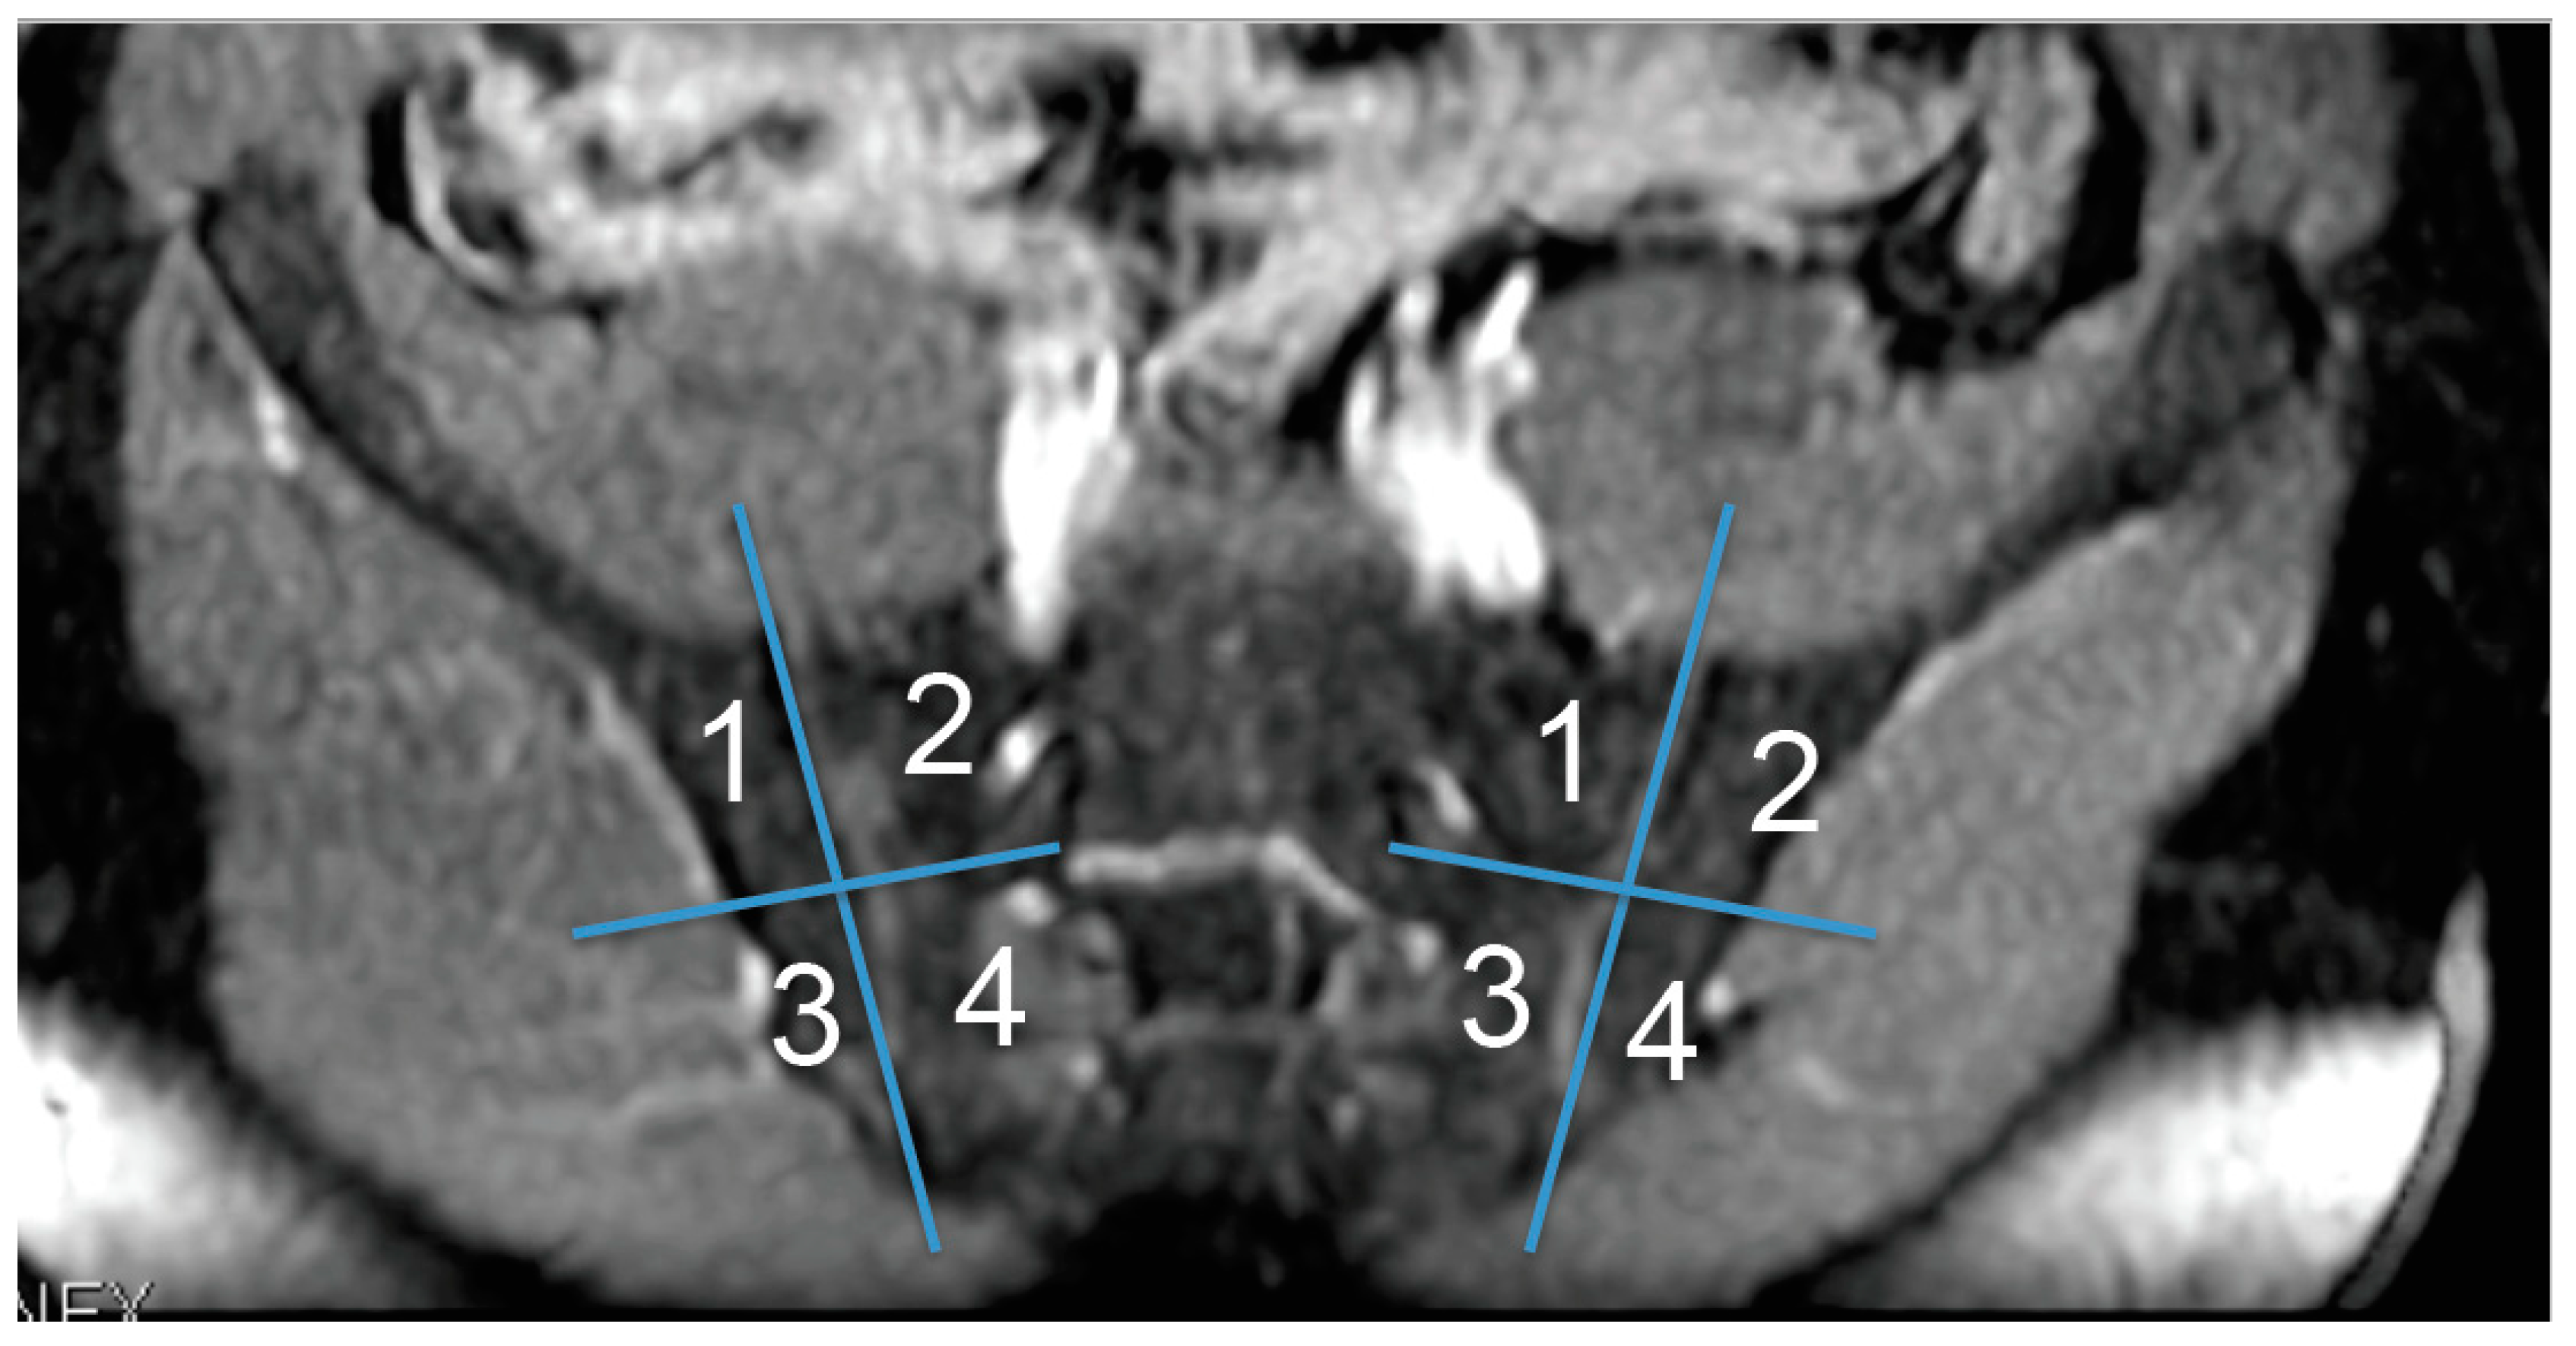

Figure 1. Subdivision of each sacroiliac joint (SIJ) into four quadrants according to a simplified SPARCC scoring system.